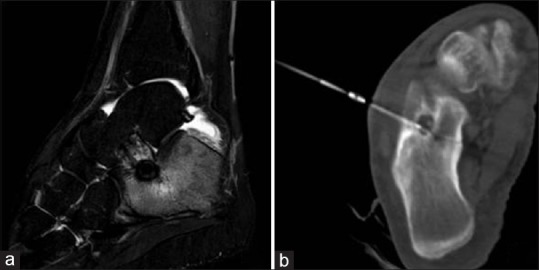

| Figure 2:A 17-year-old boy with a right calcaneal osteoid osteoma near the talocalcaneal joint margin. (a) Magnetic resonance imaging (short tau inversion recovery) sagittal image shows central nidus surrounded by hypointense reactive sclerosis. Rest of the surrounding calcaneum appear hyperintense due to reactive edema due to osteoid osteoma. (b) Computed tomography scan shows radiofrequency ablation probe in situ in nidus